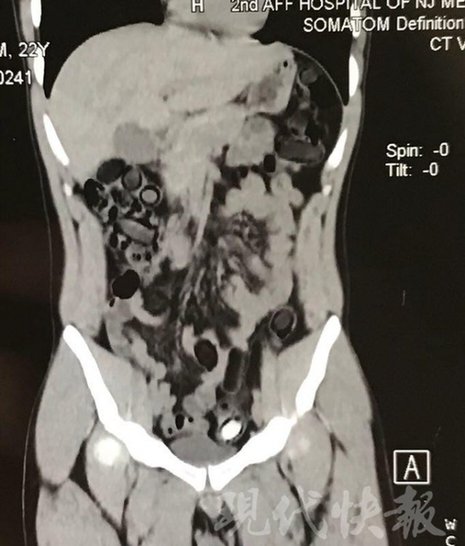

由于毒品在體內(nèi)一旦泄露有可能致命,警方第一時(shí)間將阿永帶到醫(yī)院進(jìn)行檢查。CT 掃描的結(jié)果顯示,阿永體內(nèi)布滿了密密麻麻的白色圓柱狀固體,就像一粒粒的蠶蛹。在南京市公安局鼓樓分局二板橋派出所,阿永分四次排出了毒品,毛重369.99克。經(jīng)訊問(wèn),阿永交代了自己全部的犯罪事實(shí)。目前,阿永已被刑事拘留。